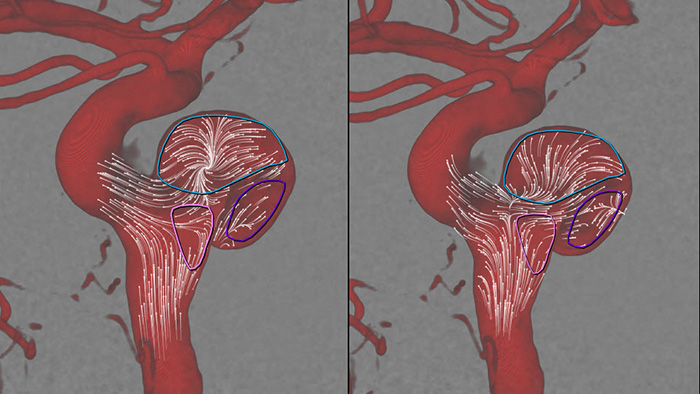

SmartCT Angio — это метод получения рентгеновского снимка, который обеспечивает полную 3D-визуализацию сосудов головного мозга с высоким разрешением с помощью единственной вращательной ангиографии, управляемой с помощью сенсорного экрана у стола. Это может улучшить видимость извилистых или сложных структур, которые, возможно, не видны на изображениях 2D или DSA.

SmartCT Angio за несколько секунд предоставляет объемные данные для просмотра и проведения оценки местоположения, размера, шейки аневризмы и тяжести состояния больного. 3D-объемные изображения визуализируются с высоким пространственным разрешением и автоматической компенсацией движений пациента.